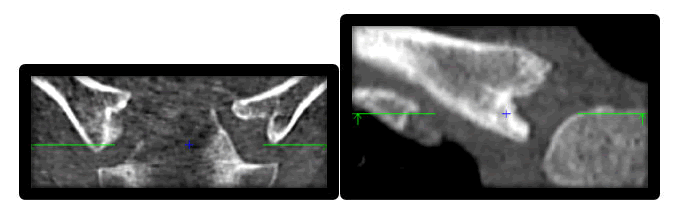

We have also studied the main sources of error in stage and substage evaluation in this study which are firstly anatomical variants: 21 scanners were rejected due to variants that do not allow classification (example: "crab claw" aspect) (Figure 1) [7,8].

Figure 1. Crab claw aspect on sternal end of the clavicle.